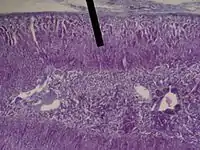

The zona fasciculata (sometimes, fascicular or fasiculate zone) constitutes the middle and also the widest zone of the adrenal cortex, sitting directly beneath the zona glomerulosa. Constituent cells are organized into bundles or "fascicles".

The zona fasciculata chiefly produces glucocorticoids (mainly cortisol in humans), which regulate the metabolism of glucose. Glucocorticoid production is stimulated by adrenocorticotropic hormone (ACTH), which is released from the anterior pituitary, especially in times of stress as part of the fight-or-flight response. The zona fasciculata also generates a small amount of weak androgens (e.g., dehydroepiandrosterone). The main source of androgens will come from the zona reticularis region. In certain animals such as rodents, the lack of 17alpha-hydroxylase results in the synthesis of corticosterone instead of cortisol.